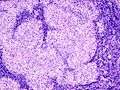

Asteroid body in sarcoidosis